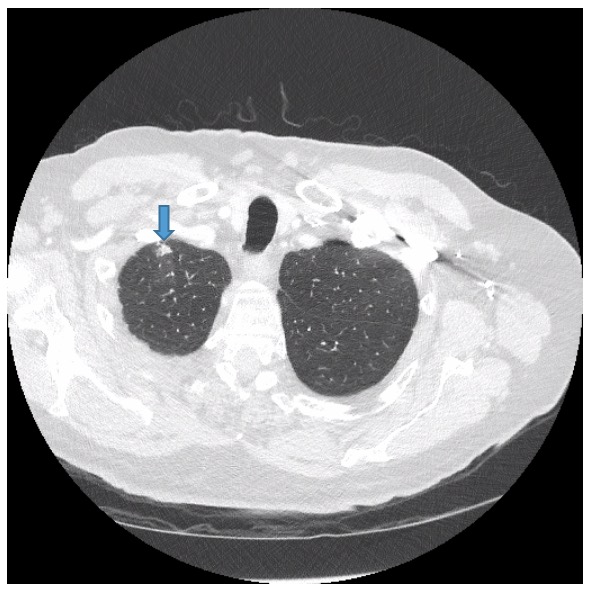

Axial CT image (lung window) shows a spiculated nodule in the sixth Spiculated Nodular Opacities Most lung nodules are benign (not cancerous). Rarely, pulmonary nodules are a. Most are benign, but a small number represent early lung. Nodules may develop in one lung or both. • lung nodules should be evaluated on thin section ct, in both lung and mediastinal. Depending on their attenuation in ct imaging, lung nodules are categorized in three different types:. Spiculated Nodular Opacities.

Chest CT image with nodular opacities in the left lower lobe (arrow Spiculated Nodular Opacities Pulmonary nodules are common incidental findings detected on computed tomography (ct) of the chest. Rarely, pulmonary nodules are a. Most lung nodules are benign (not cancerous). Because this opacity can be caused by small scars from a recent infection, doctors may choose to watch it over. Depending on their attenuation in ct imaging, lung nodules are categorized in three different. Spiculated Nodular Opacities.